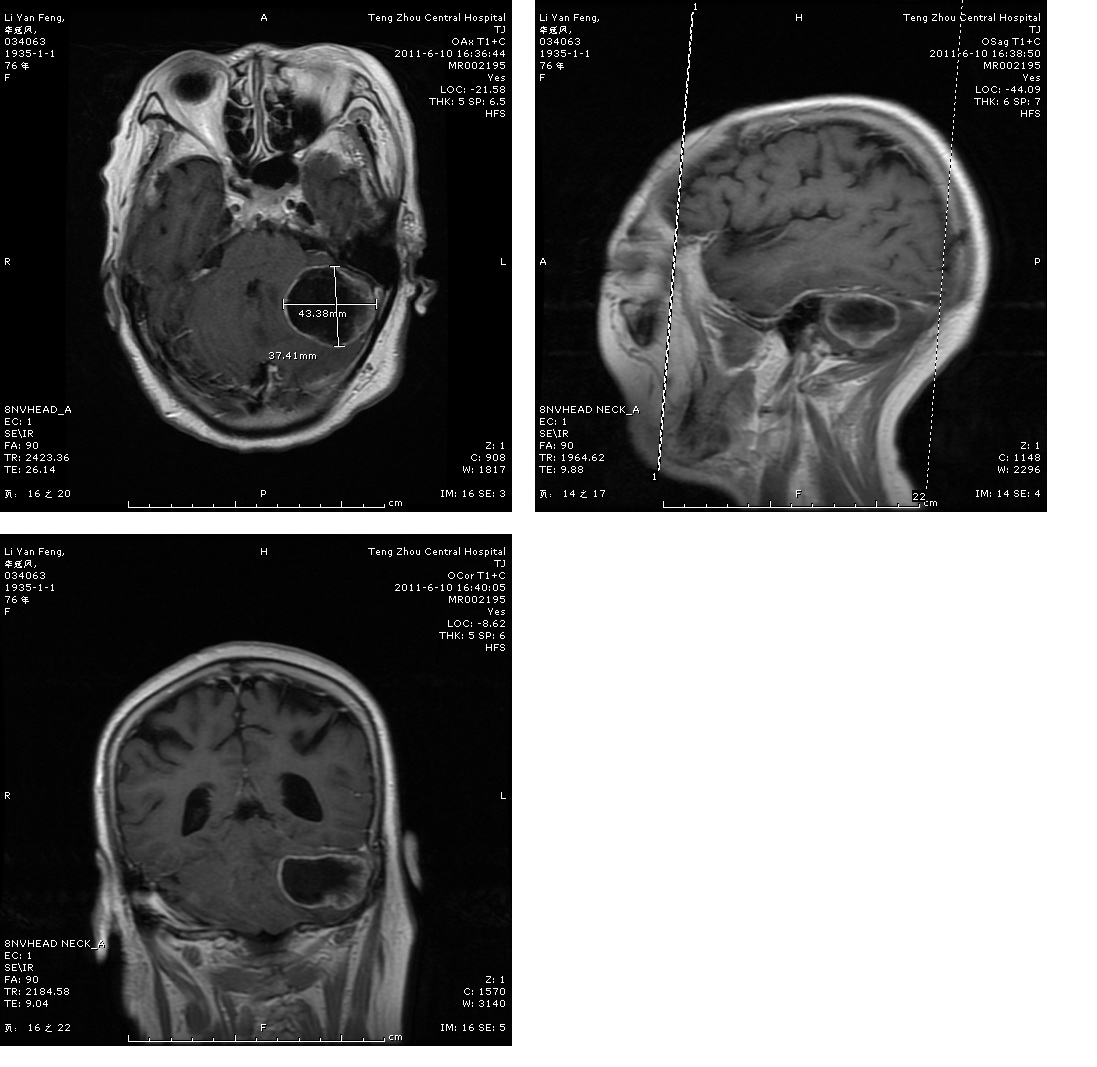

轉(zhuǎn)移瘤切除術(shù)前

轉(zhuǎn)移瘤切除術(shù)后